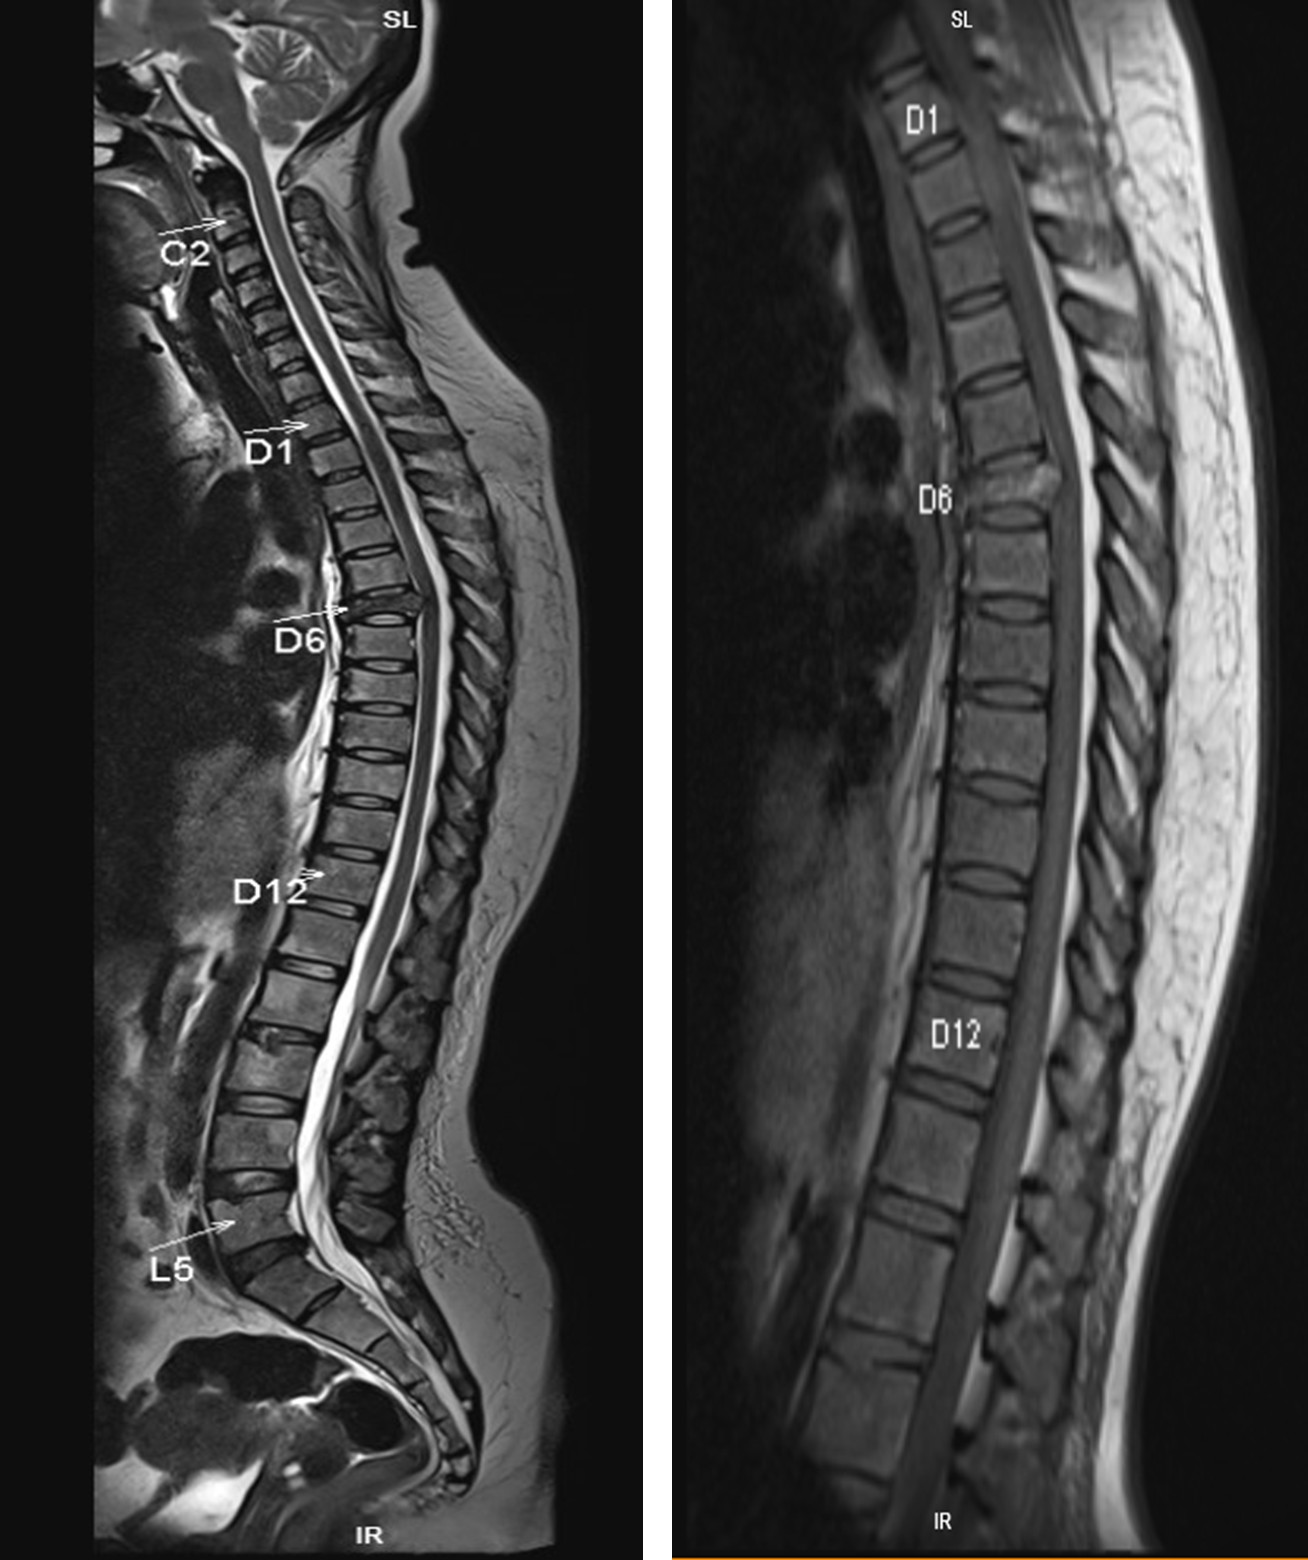

MRI Whole Spine

Multiple focal lesions involving the vertebrae, sternum, pelvic bones and both femur with reduction in height of the D6 vertebra with disruption of the posterior cortex with retropulsion causing significant thecal sac and cord compression with altered signal intensity within it. – To consider: multiple bone secondaries.